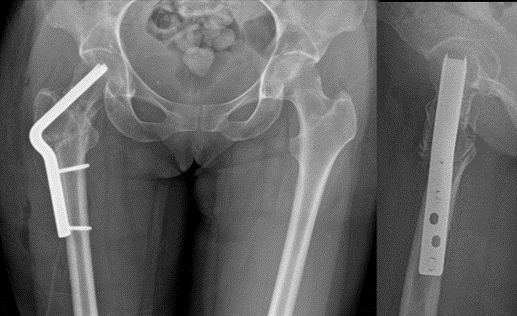

1 yr follow-up xrays. Both the femoral neck nonunion & the #osteotomy were healed by 3 mos. Pt has returned to all activities & has no pain🙌This operation, although originally described by Pauwels almost 100 yrs ago, is just as relevant & elegant today!